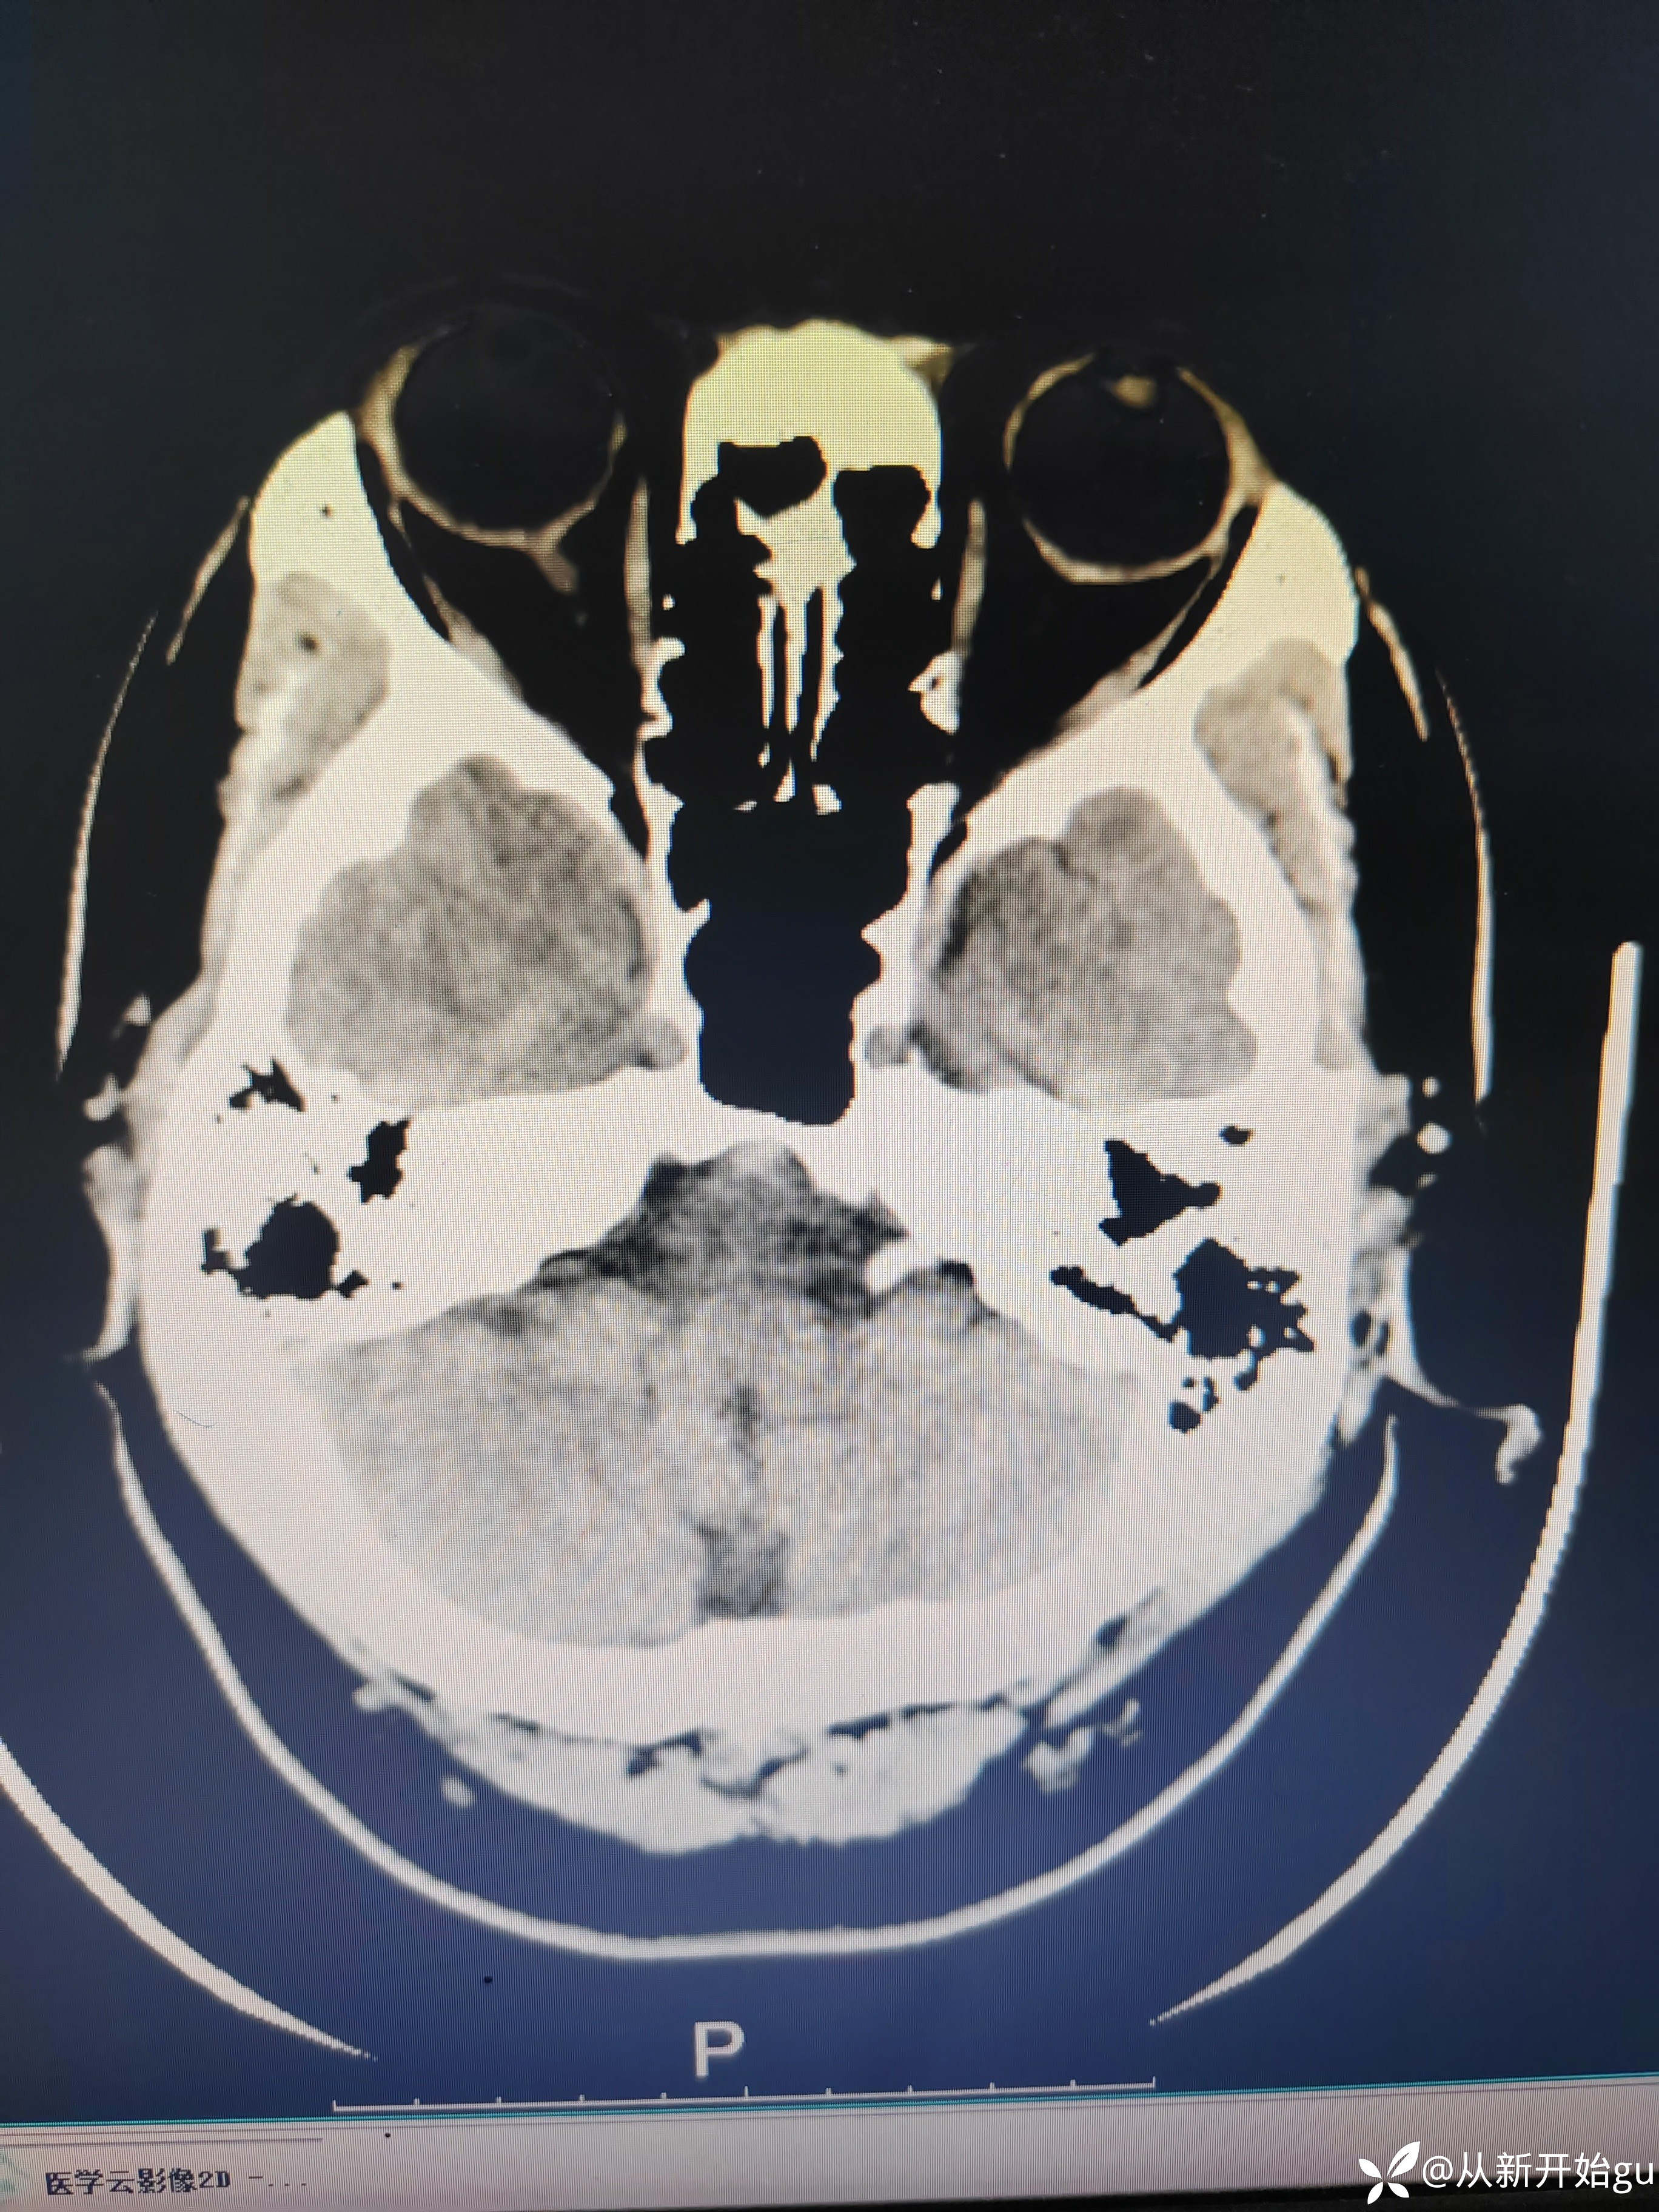

患者51岁男性,主因左下肢活动障碍1小时来院。既往高血压病史,查体,右侧鼻唇沟稍浅(家属诉之前就这样),神舌居中,左侧下肢肌力5级-,左侧跟膝胫试验欠稳准,左侧巴氏征阳性,评分也就一分,鼻唇沟稍浅未纳入。行颅脑CT检查如图所示